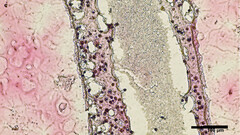

Cientistas da Universidade de British Columbia (UBC) conseguiram imprimir réplicas em 3D de estruturas tubulares produtoras de esperma feitas a partir de células testiculares viáveis. O material de bioimpressão foi coletado através de biópsia de células-tronco testiculares de pacientes que têm azoospermia não-obstrutiva (NOA), a forma mais pesada de infertilidade masculina. Essas protocélulas foram então cultivadas e multiplicadas antes de serem impressas em 3D, formando uma estrutura tubular semelhante à dos espermatozóides localizados em testículos humanos

Não apenas o método de bioimpressão foi bem sucedido em termos de sobrevivência celular, mas após 12 dias os tubos foram examinados e o material "amadureceu em várias das células especializadas envolvidas na produção de esperma". Além disso, os falsos tubos testiculares "estavam mostrando uma melhora significativa na manutenção das células-tronco espermatogoniais - ambos sinais iniciais de capacidade de produção de esperma", diz o relatório. De acordo com o pesquisador principal do estudo, o professor assistente de urologia da UBC, Dr. Ryan Flannigan:

O objetivo da equipe de pesquisa agora é experimentar a alimentação das células bioimpressas com vários nutrientes e fatores de crescimento adequados, a fim de enganá-los na produção viável de espermatozóides que poderiam posteriormente ser utilizados em novos tratamentos de infertilidade para casais que tentam engravidar.